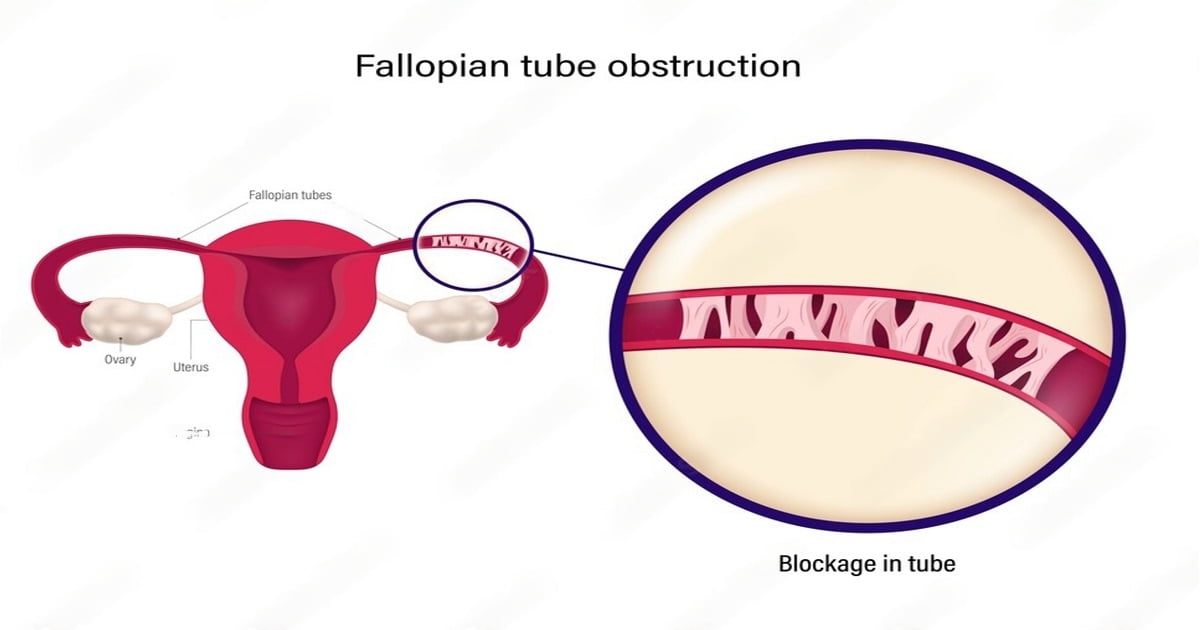

Blocked Fallopian Tubes Causes Symptoms And Treatment

Blocked Fallopian Tubes Symptoms Causes And Treatment

FTR Symptoms And Causes Of Blocked Fallopian Tubes Fibroid